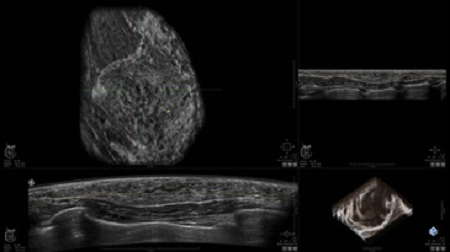

УЗИ-аппарат

GE INVENIA ABUS 2.0

GE INVENIA ABUS – это современный УЗИ аппарат, который создан для точной и эффективной диагностики сканирования с высокой плотностью молочных желез. Выявляемость патологий раковых и предраковых стадий заболевания составляет 55%, что в конечном счете позволяет ставить врачу точные и своевременные диагнозы. Традиционные методы использования маммографии не показывают такой выявляемости, ограничиваясь лишь 3-38%.

УЗИ-аппарат GE INVENIA ABUS позволяет проводить максимально операторонезависимые процедуры, что значительно снижает риск неправильной постановки диагноза и сопутствующие издержки на обработку информации. Система готовит отчет в течение 3-х минут после сканирования, это безусловное преимущество по сравнению с обычным УЗИ сканером.

Данное устройство классифицируется, как стационарное, используемое в многопрофильных клиниках, женских консультациях, медицинских центрах. Вес без учета дополнительного оборудования составляет 105 кг. Удобная колесная база позволяет оперативно маневрировать в ограниченных пространствах, в том числе передвигать устройство в коридорах клиники. Большой 17-ти дюймовый монитор с широкими углами обзора выводит максимально качественную картинку в формате Full HD.

Возможности встроенной УЗ-системы:

• Увеличение или уменьшение степени сжатия грудной железы;

• Функция автоматического сканирования активируется одним нажатием;

• Возможность отмены сканирования;

• Глубина проникновения УЗ-лучей – до 50 мм;

• Одно детализированное изображение можно получить менее чем за 1 минуту

• Многорядная светодиодная подсветка;

• Встроенный сверхширокий вогнутый датчик С15-6ХW.